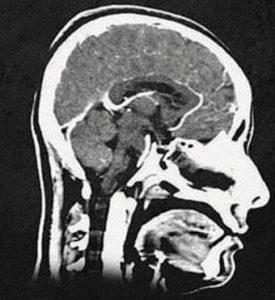

| MRI

|

Magnetic resonance imaging (MRI) produces “slices” that represent the human body through the application of magnetic signals. It lasts longer than a CT and is more detailed | – High- and – Very-high-field

-Low-to-mid-field – Ultra-high-field |

– Cardiology

– Vascular – Musculoskeletal – Neurology - Mom |